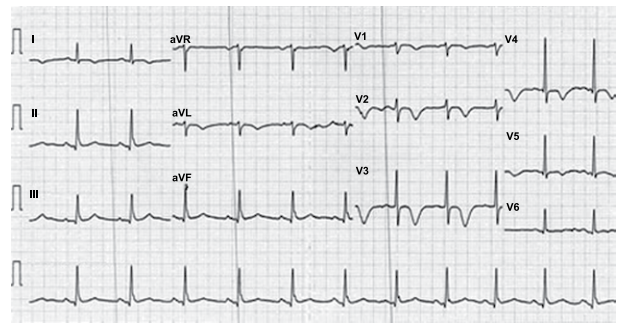

Paciente do sexo feminino, 66 anos, com antecedentes de tabagismo, hipertensão arterial sistêmica e diabetes mellitus tipo 2, procura atendimento médico com queixa de desconforto retroesternal tipo queimação e opressão que se iniciou há 1 mês, desencadeado aos grandes esforços. Há 1 semana passou a apresentar os mesmos sintomas em repouso, associados à dispneia, com duração de até 8 minutos e melhora espontânea. A paciente faz uso de valsartana 80 mg, glimepirida 4 mg e metformina 1000 mg. O exame físico é normal, PA = 150x85 mmHg e frequência cardíaca de 96 bpm. O eletrocardiograma está ilustrado a seguir.

Paciente do sexo feminino, 66 anos, com antecedentes de tabagismo, hipertensão arterial sistêmica e diabetes mellitus tipo 2, procura atendimento médico com queixa de desconforto retroesternal tipo queimação e opressão que se iniciou há 1 mês, desencadeado aos grandes esforços. Há 1 semana passou a apresentar os mesmos sintomas em repouso, associados à dispneia, com duração de até 8 minutos e melhora espontânea. A paciente faz uso de valsartana 80 mg, glimepirida 4 mg e metformina 1000 mg. O exame físico é normal, PA = 150x85 mmHg e frequência cardíaca de 96 bpm. O eletrocardiograma está ilustrado a seguir.

Homem, 46 anos, com antecedente de infarto agudo do miocárdio, é portador de miocardiopatia isquêmica e insuficiência cardíaca. Atualmente recebe tratamento otimizado para insuficiência cardíaca, no entanto permanece em classe funcional III (NYHA). O ecocardiograma mostra diâmetro diastólico do ventrículo esquerdo = 72 mm e fração de ejeção do VE = 34%. Holter de 24 horas: extrassístoles ventriculares frequentes, quatro episódios de taquicardia ventricular não sustentada e um episódio de taquicardia ventricular sustentada com 1 minuto de duração. O eletrocardiograma está ilustrado a seguir.